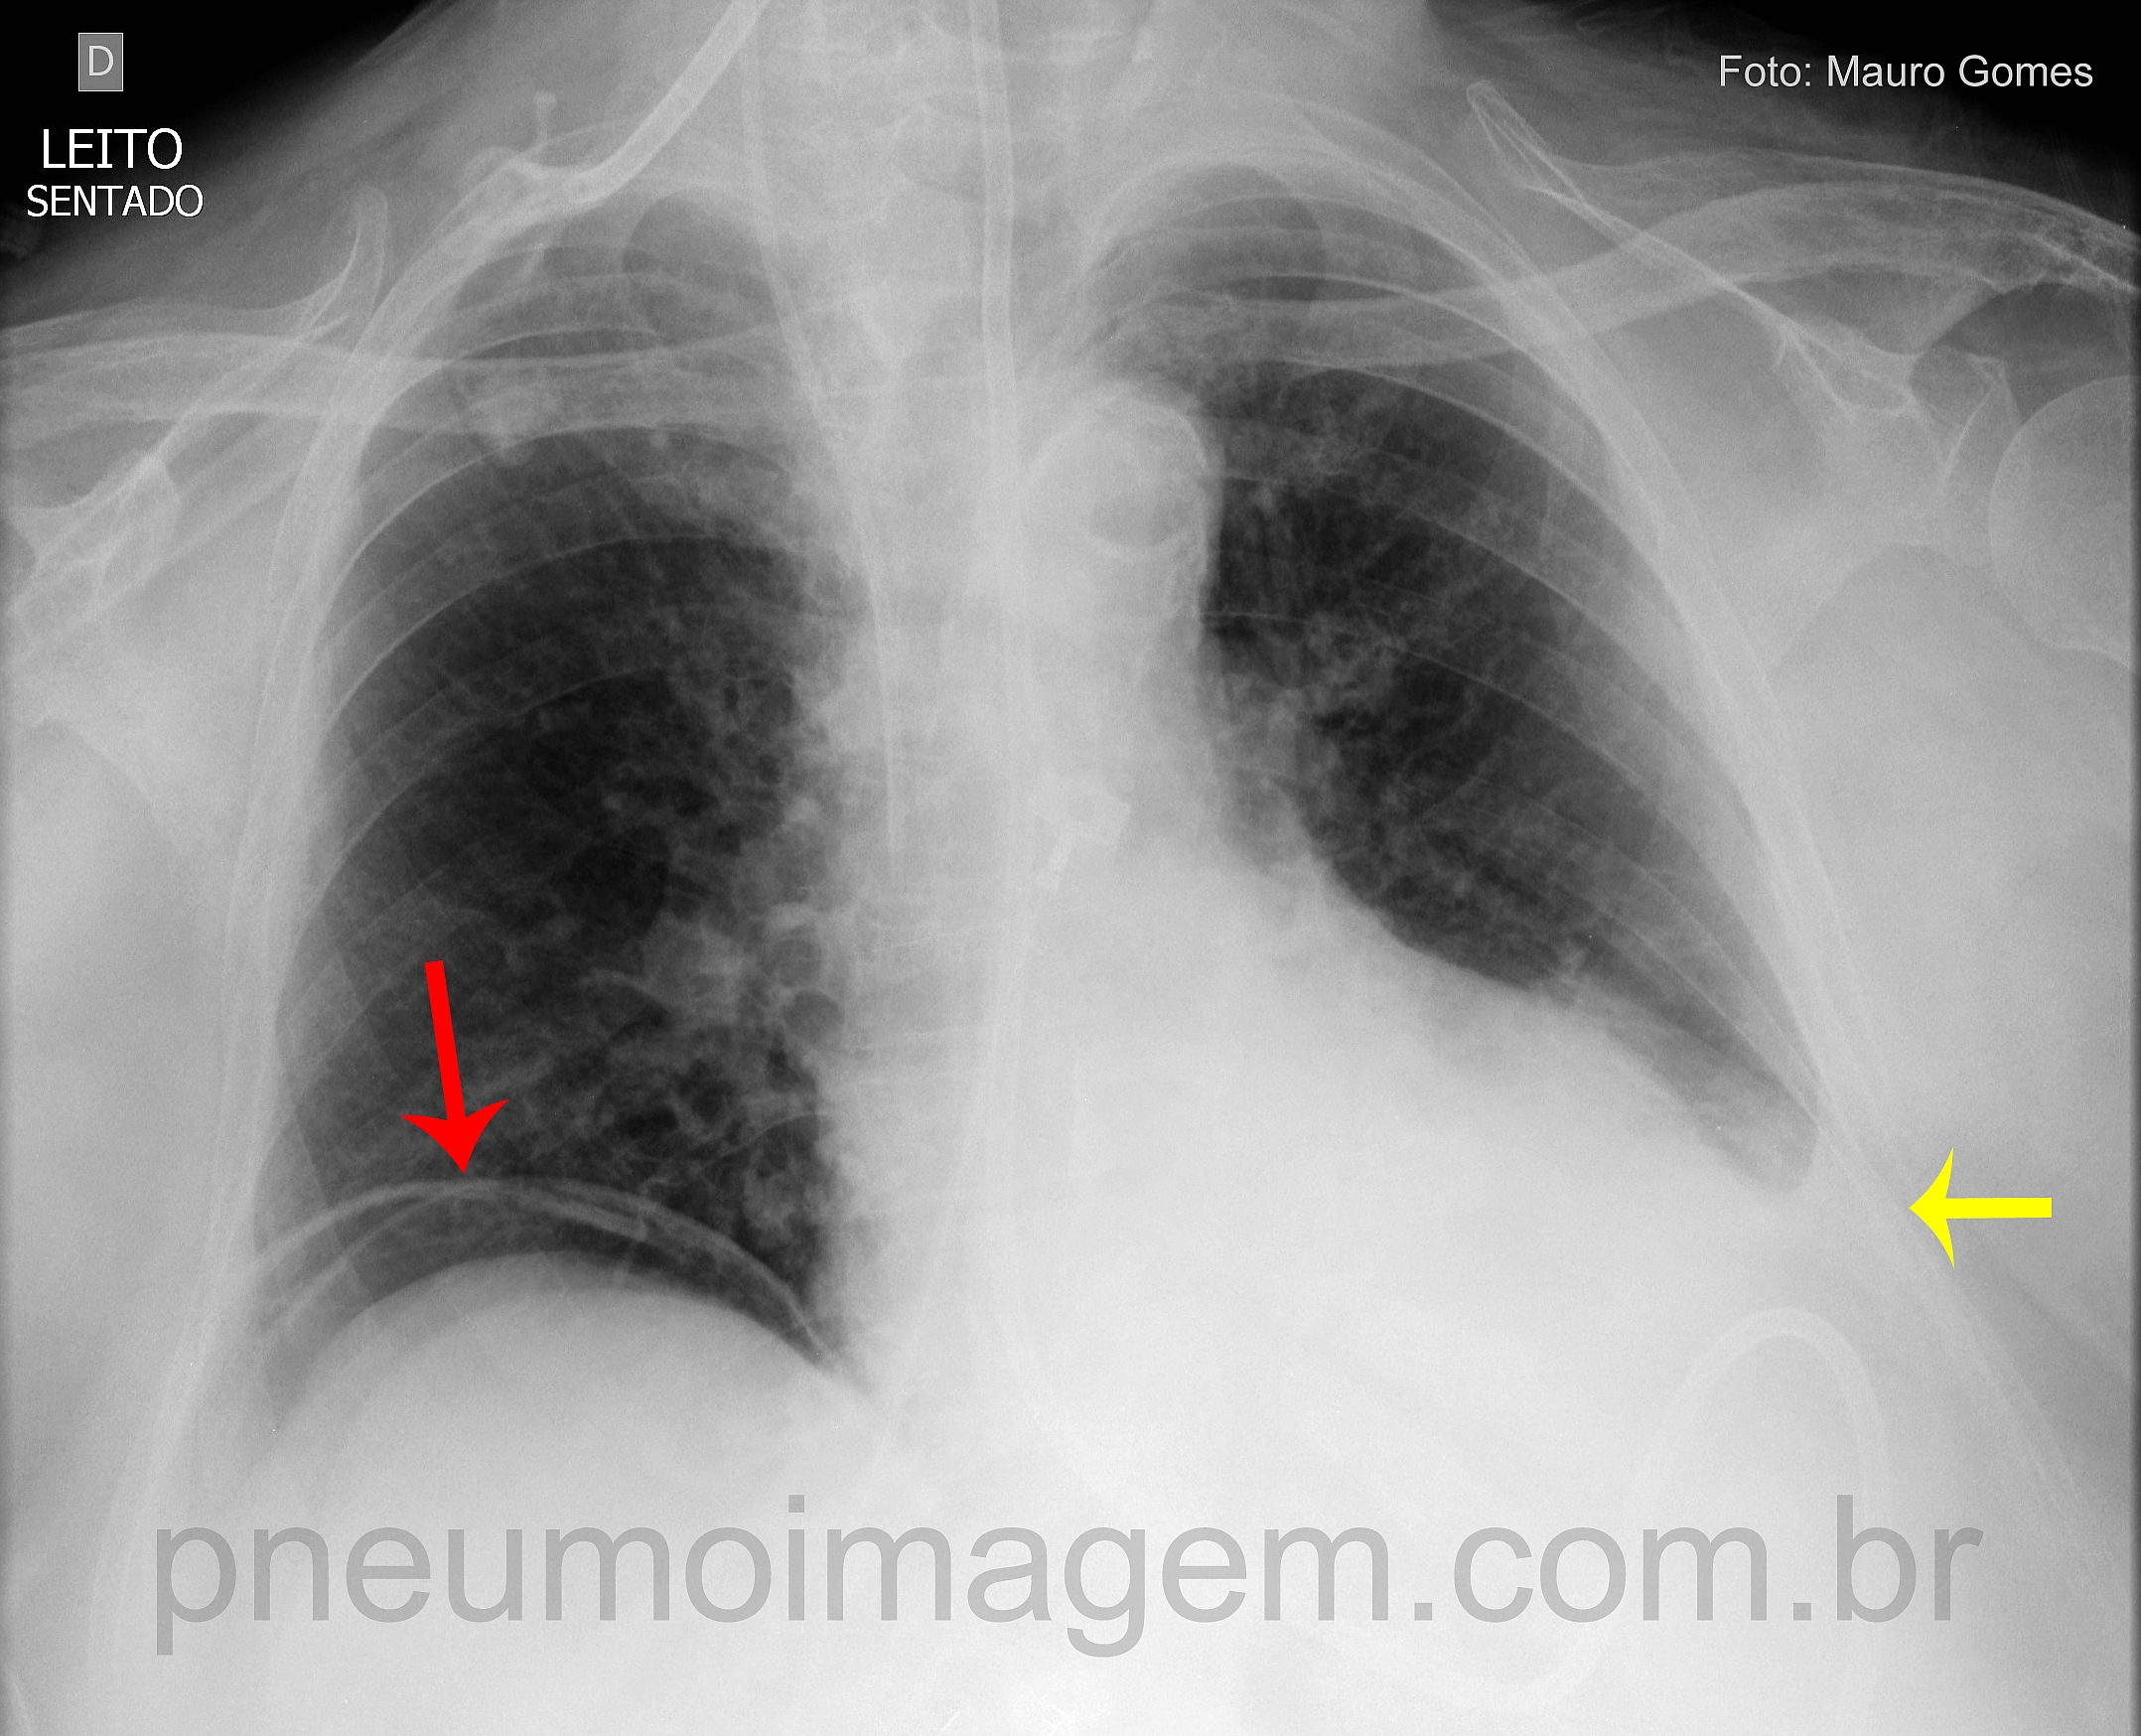

CASO CLÍNICO #39O que as setas apontam nessa radiografia? Deixe os seus comentários abaixo!

What the arrows point in this chest X? Give your comments below!